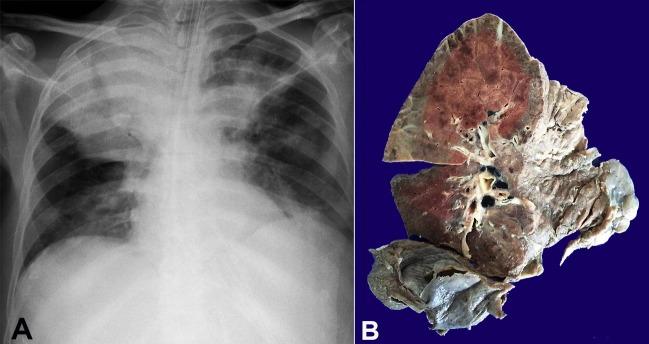

In the advanced stage of AIDS, the diagnosis of the opportunistic infections may be challenging due to the high risk of performing invasive diagnostic methods in a patient with a critical clinical condition, as well as the correct interpretation of the results of microbiological exams. One of the challenges for the diagnosis and treatment of the opportunistic infections is that they may occur concomitantly in the same patient and they may mimic each other, leading to a high discrepancy between clinical and autopsy diagnoses. We describe the case of a 52-year-old man who was hospitalized because of weight loss, anemia, cough, and hepatosplenomegaly. During the investigation, the diagnosis of AIDS was made, and the patient developed respiratory failure and died on the fourth day of hospitalization. At autopsy, disseminated non-tuberculosis mycobacteriosis was found, affecting mainly the organs of the reticuloendothelial system. Also, severe and diffuse pneumonia caused by multiple agents ( , , suppurative bacterial infection, non-tuberculosis mycobacteria, and cytomegalovirus) was seen in a morphological pattern that could be called "collision pneumonia." The lesson from this case, revealed by the autopsy, is that in advanced AIDS, patients often have multiple opportunistic infections, so the principle of Ockham's razor-that a single diagnosis is most likely the best diagnosis-fails in this clinical context.

在艾滋病晚期,由于对处于危急临床状况的患者进行侵入性诊断方法存在高风险,以及对微生物学检查结果的正确解读,机会性感染的诊断可能具有挑战性。机会性感染的诊断和治疗面临的挑战之一是,它们可能在同一患者中同时发生,并且可能相互模仿,导致临床诊断与尸检诊断之间存在很大差异。我们描述了一名52岁男性因体重减轻、贫血、咳嗽和肝脾肿大而住院的病例。在调查过程中,确诊为艾滋病,患者出现呼吸衰竭并在住院第四天死亡。尸检发现播散性非结核分枝杆菌病,主要影响网状内皮系统的器官。此外,还发现由多种病原体( 、 、化脓性细菌感染、非结核分枝杆菌和巨细胞病毒)引起的严重弥漫性肺炎,其形态学模式可称为“碰撞性肺炎”。尸检揭示的这个病例的教训是,在晚期艾滋病患者中,常常存在多种机会性感染,因此在这种临床情况下,奥卡姆剃刀原则(即单一诊断最有可能是最佳诊断)并不适用。